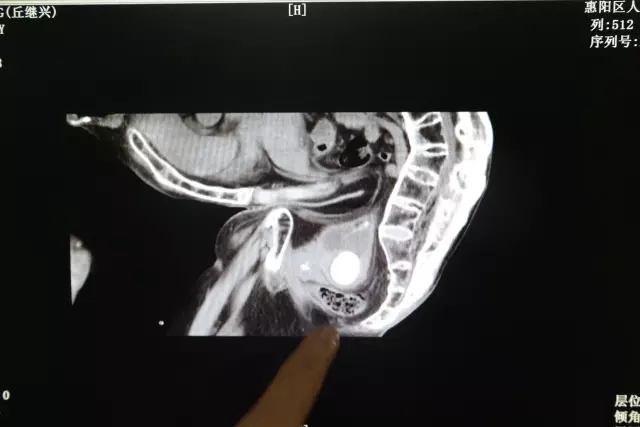

我院泌尿外科接診後(hòu)經(jīng)檢查發(fā)現,老伯的膀胱結石已經(jīng)達到直徑4cm,嚴重堵塞尿道(dào)口,緻使他排尿困難,尿路感染嚴重。泌尿外科團隊經(jīng)過(guò)慎重的考慮,認爲手術治療可采用超聲腔内碎石系統,進(jìn)行微創碎石。我院在9月引進(jìn)微創新技術已經(jīng)成(chéng)功治愈幾十名相似病例的患者,技術成(chéng)熟,雖然老人的病例特殊,手術難度大,但我院泌尿外科團隊有能(néng)力有信心爲老伯解決痛苦。

據鍾主任介紹說(shuō),老伯患有嚴重的強直性脊柱炎,腰呈90度彎曲,盆腔與大腿貼到一塊,沒(méi)辦法伸直,按照正常的體位經(jīng)腹取石不可行,隻能(néng)經(jīng)尿道(dào)取石,而且老伯年紀大了,麻醉也是個大難題,經(jīng)過(guò)泌尿外科、麻醉科的專家們多次會(huì)診後(hòu),制定了治療方案。